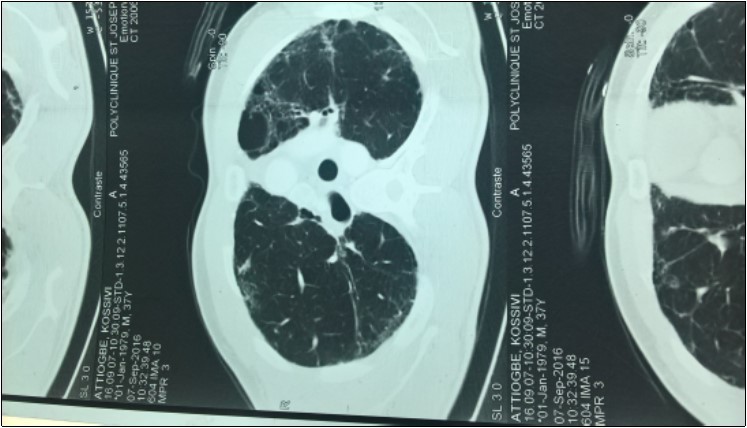

Mr ATT Kos is a 44-year-old patient receiving neurological consultation for dyspnea and sensation of generalized muscle weakness worsening on exertion. The onset of the symptoms dates back to August 2005 marked by the progressive installation of a dyspnea of effort without the notion of cough or slimming. There was no associated infectious context. A consultation in pneumology made it possible to classify his dyspnea at stage I of Sadoul. After a chest radiograph that was normal, he had a thoracic CT scan that revealed multiple bubbles of bilateral emphysema. The patient was then given corticosteroids and beta 2 mimetic. The development was marked by a discreet improvement in dyspnea. The patient again consults with the persistence of dyspnea and a fatigability to the usual effort with modification of the timbre of the voice. This consultation made on December 29, 2016 had made it possible to find episodes of rare false roads as well as a ptosis in case of extreme fatigue. Clinical examination was normal. The diagnosis of myasthenia gravis was then discussed. The detection of anti-receptor anti-acetylcholine antibodies (Ac Anti RACH) was positive with a titre of 0.8 nmol / ml (normal less than 0.2 nmol / ml.) The electromyogram showed a moderate decrease in motor potential at The repetitive stimulation was of the order of 9% .The mediastinum scan showed bilateral pulmonary fibrosis (Figure 1) in relation to its progressive pulmonary pathology and a prostigmine test was performed during a fatigue episode associated with A ptosis and a marked regression of the signs The examination of the patient by a pulmonologist revealed that his present dyspnoea was in Stage II of SAOUL Spirometry reported a 52% FVCI, 63% FEV 1 EFF To 118%, with no improvement in the beta 2 mimetic parameters, and the gasometric data were: PaO2 = 59%, PaCO2 = 54%, PH = 7.39 Hb = 14.3 and HCO3 = 32 The association of myasthenia gravis and fibrosis Motivated by the search for antinuclear antibody: negative; Anti-tRNA-synthetase antibody: positive for anti-PL7 and negative for anti-PL12; Negative also for anti-EJ and anti-OJ. Anti-KU and anti-Pm / Scl antibodies were also negative. Anti-synthetase syndrome has been retained in our patient. It was then placed on Pyridostigmine at progressive dose and Prednisolone at degressive dose. This treatment allowed a stabilization of the clinical state of the patient.